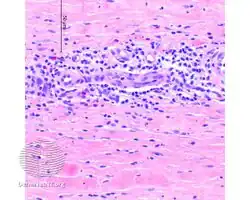

Eosinophilic fasciitis/pathology